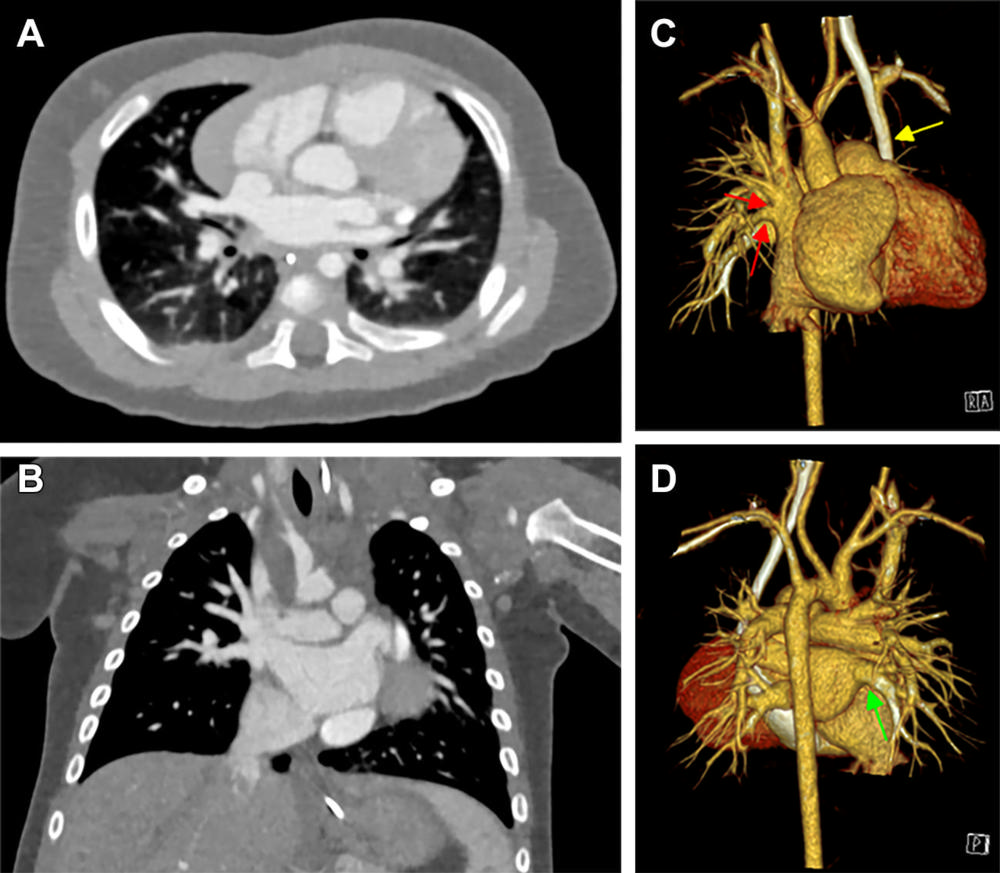

Figure 1. Cardiac photon-counting CT (PCCT) in a 174-day-old male infant with complex congenital heart defect. (A) Contrast-enhanced axial PCCT image shows sonographically suspected sinus venosus defect with partial anomalous pulmonary venous connection. (B) Contrast-enhanced coronal PCCT image. (C) Anterior view of three-dimensional reconstruction shows a partial anomalous pulmonary venous connection of two separate lung veins from the right upper and middle lobe to the right superior vena cava (red arrows) and a persisting left superior vena cava (yellow arrow). (D) Three-dimensional reconstruction, posterior view. The diagnosis was confirmed at PCCT, and PCCT allowed for visualization of the partial anomalous pulmonary venous connection of two separate lung veins from the right upper and middle lobe to the right superior vena cava. One lung vein drains correctly to the left atrium (green arrow). A sinus venosus defect, an atrial septum defect, an enlarged right atrium and a persisting left superior vena cava are shown. The only regular confluence of a single right lung vein into the left atrium is shown (D; green arrow). Image quality was rated as 5 of 5 (optimal).